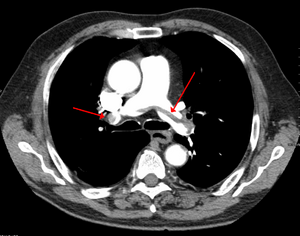

| Chest spiral CT scan with radiocontrast agent showing multiple filling defects both at the bifurcation ("saddle" pulmonary embolism) and in the pulmonary arteries. | |

CT pulmonary angiography showing a "saddle embolus" at the bifurcation of the main pulmonary artery and thrombus burden in the lobar arteries on both sides.